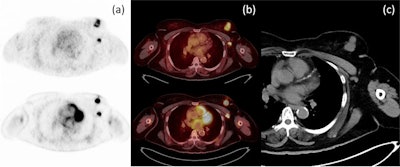

Axial PET (a) and axial fusion (b) images of F-18 FES (top) and F-18 FDG (bottom) with concordant uptake of both radiotracers in a left breast mass and left axillary node metastasis in correlation with CT imaging (c). Image courtesy of the European Journal of Hybrid Imaging.Image courtesy of the European Journal of Hybrid Imaging.